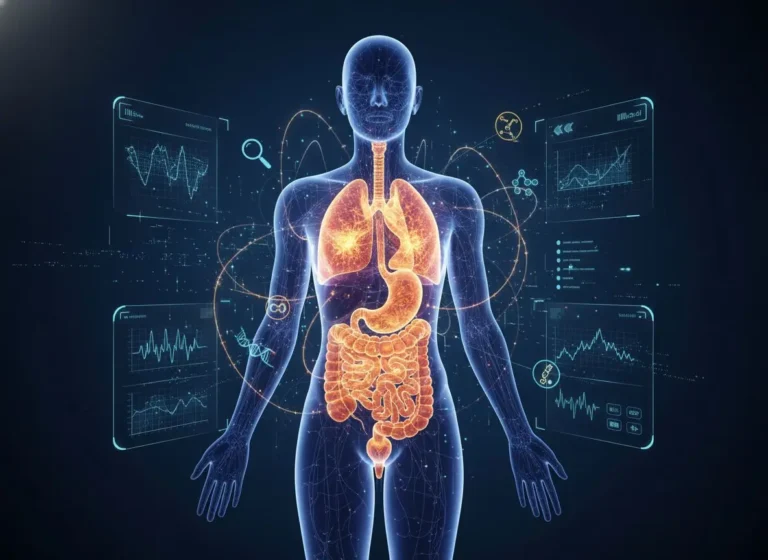

The journey starts here, opening doors to deeper understanding Cancer is not just a medical condition it is a life-altering journey that…

You don’t know how strong you are until being strong is the only choice you have The field of cancer surgery has…

A Personal Message for Anyone Facing Cancer If you’re reading this because you or someone you love has been diagnosed with cancer,…